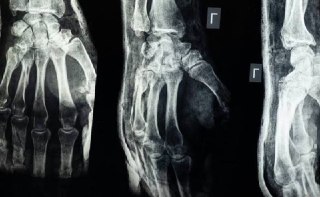

Команда китайських вчених створила новий вид медичного клею «Bone-02» для швидкого відновлення зламаних кісток. Клей м...